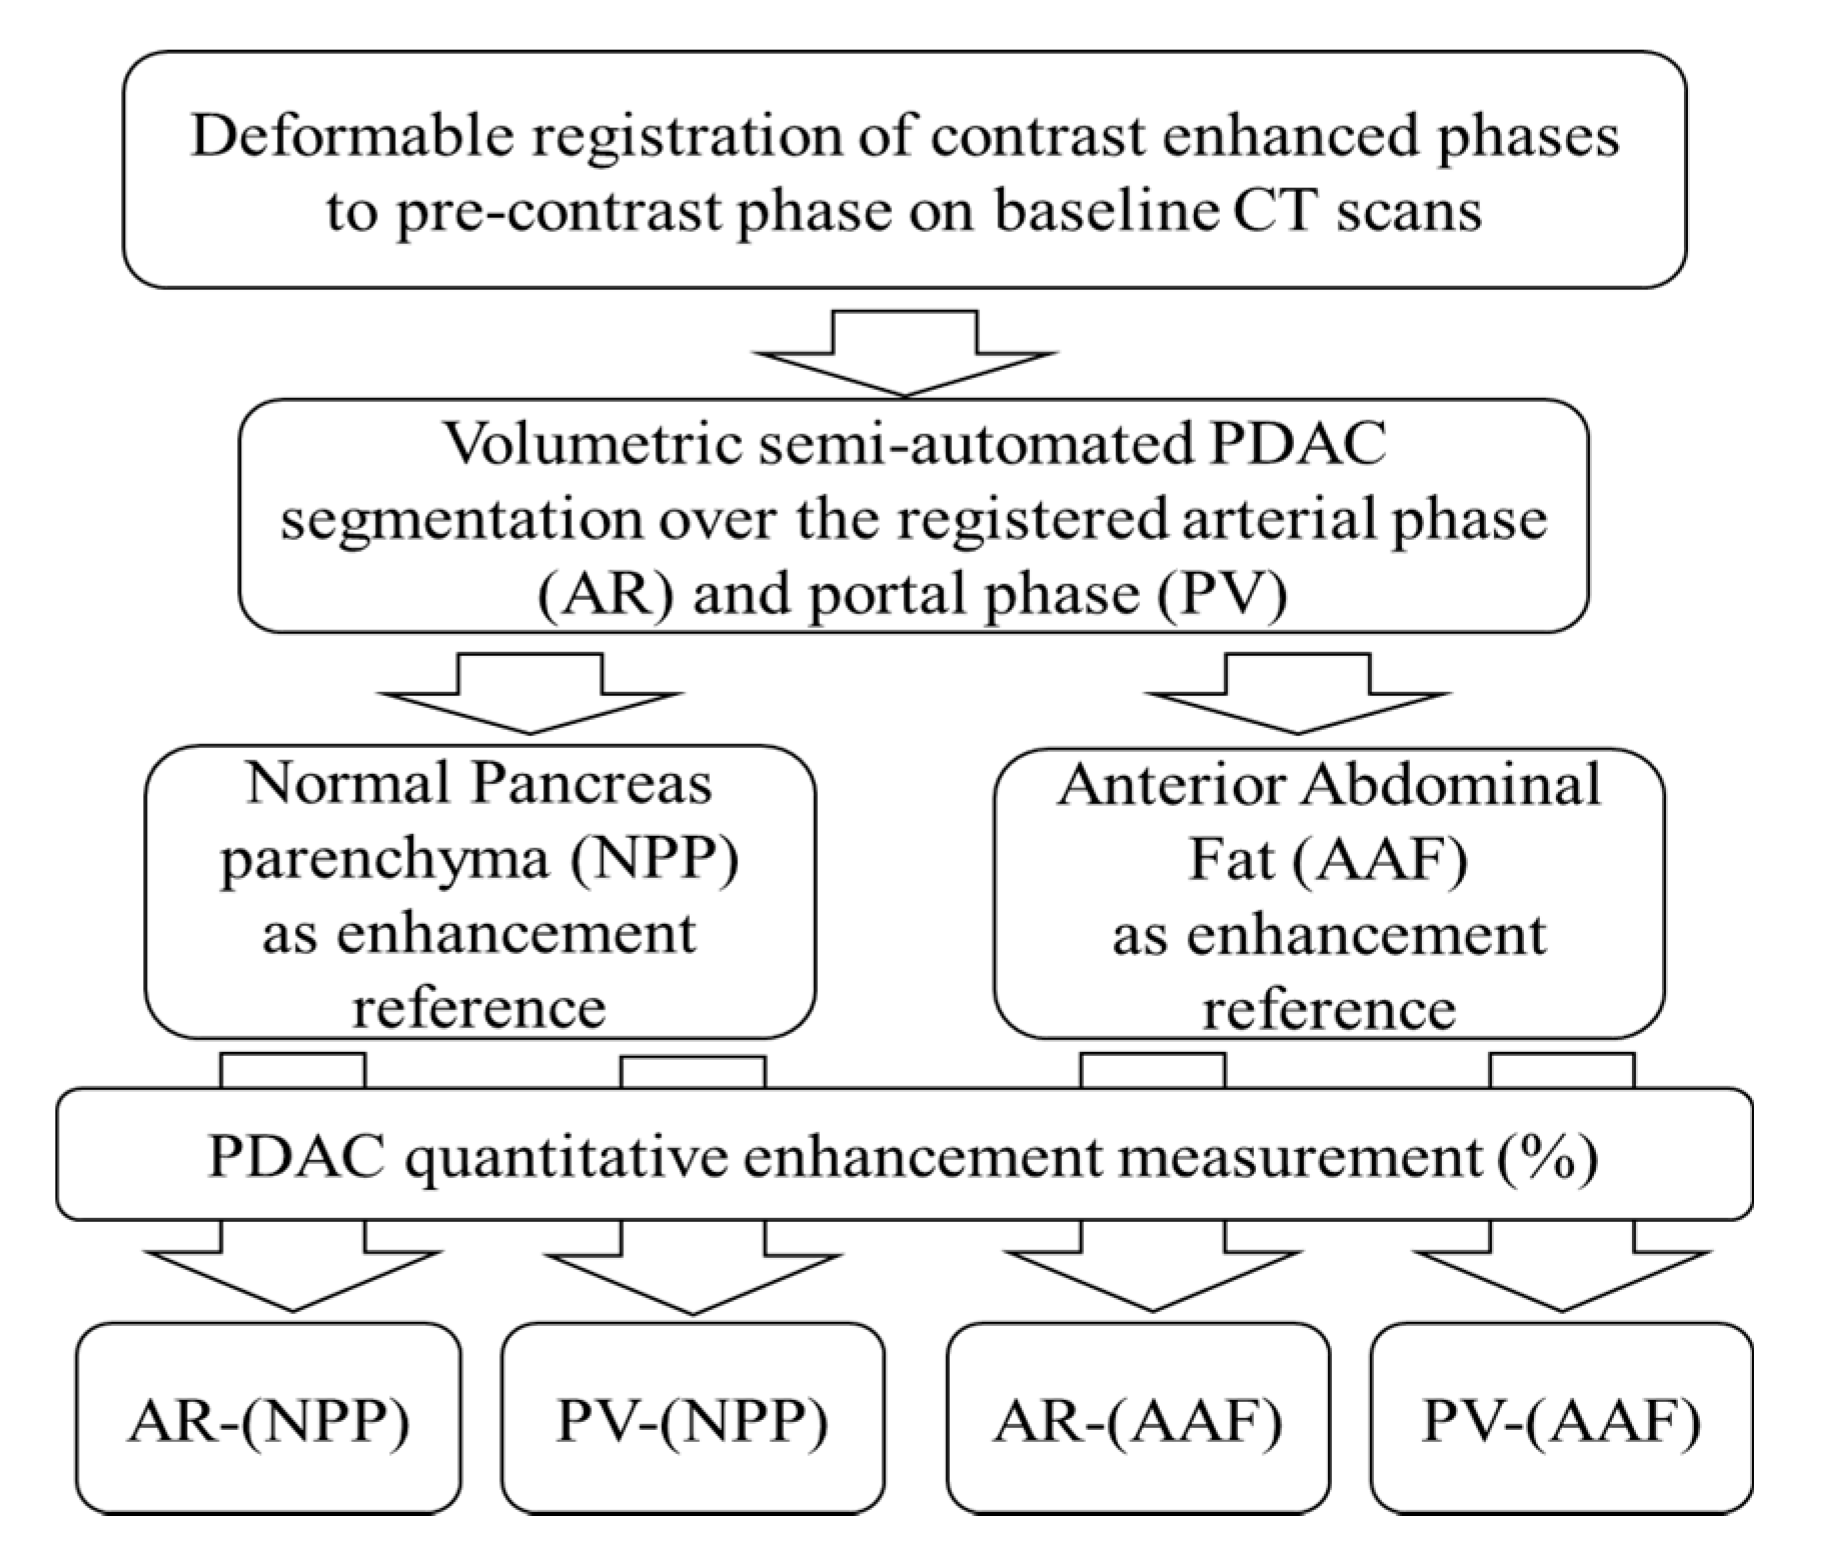

4.3. CT Analysis: Normalized Area under the Curve (nAUC)

4.5. CT Analysis: Quantitative Normalized Enhancement (q-delta)